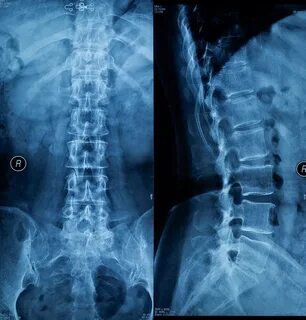

Что видно на рентгене позвоночника?

Рентгенограмма позвоночника дает врачу ценную информацию о состоянии костных структур:

- Позвонки: Видна их форма, размеры, контуры, наличие остеофитов (костных разрастаний), деформаций, клиновидных изменений (например, при остеопорозе или переломах).

- Межпозвонковые промежутки: Можно оценить высоту межпозвонковых дисков (косвенно, так как сами диски на рентгене не видны, но снижение их высоты указывает на дегенеративные изменения). Сужение межпозвонковых промежутков часто является признаком остеохондроза.

- Искривления позвоночника: Сколиоз (боковое искривление), кифоз (усиление грудного изгиба), лордоз (усиление поясничного изгиба) – все эти деформации четко видны на рентгенограммах.

- Смещение позвонков (спондилолистез): Четко видна степень смещения одного позвонка относительно другого.